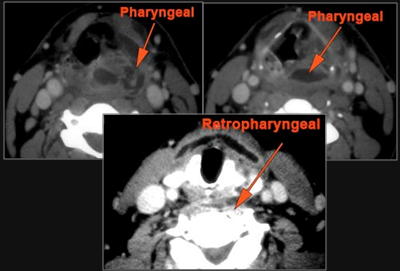

Hypopharynx, Larynx, Deep Neck and Entire Retropharyngeal Space

There is edema/abscess arising from the hypopharynx, larynx, thyroid gland or trachea.

There is edema/abscess within the adjacent deep neck, and/or retropharyngeal space.